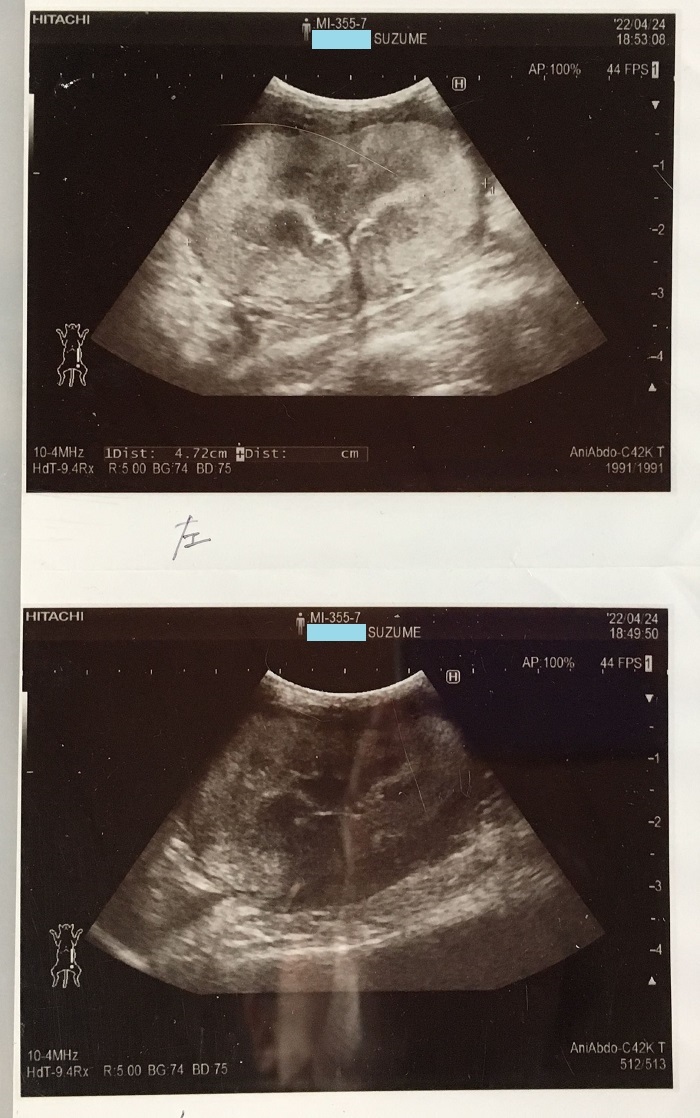

場所⑤にいたすずめがFIPを発症しました。

しかし診察した行きつけ病院の先生からは、口内疾患よりも重篤な黄疸の症状を指摘され、入院して詳しい検査を受けました。

2022/04/25

その結果、FIPの疑いが濃厚と診断され、たまっていた胸水を抜いて、確定診断の検査にまわすことになりました。

連休にかかることもあり、結果が出るまで一週間前後かかりそうということと、行きつけ病院では未承認治療薬を取り扱っていないため、対応は対症療法しかできず、その場合は、よく覚えていないのですが、二週間とか二ヶ月とか、そのくらいで死に至ることを告げられました。

そのため診断結果を待たずに、FIPの治療薬を取り扱う他の病院を予約しました。

FIPを発症するのは若い猫という印象があったため、3才を超すすずめがそうなるとは、考えてもみませんでした。

たいへん高額の治療費と薬剤費がかかることは知っていましたが、迷う時間はありませんでした。